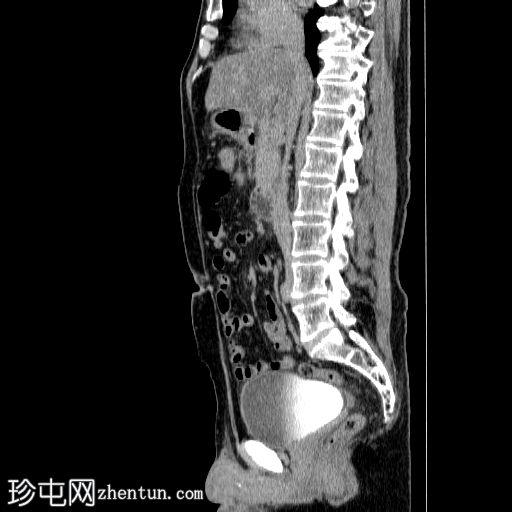

矢状面

非造影

胰体尾弥漫性增大,特征为胰腺实质低强化,无明显坏死区域。

病变横向延伸至左前肾旁间隙,伴有Gerota筋膜增厚。

病变向下延伸至盆腔。

无肠系膜或脾脏血管阻塞的证据。

未见导管扩张或钙化。